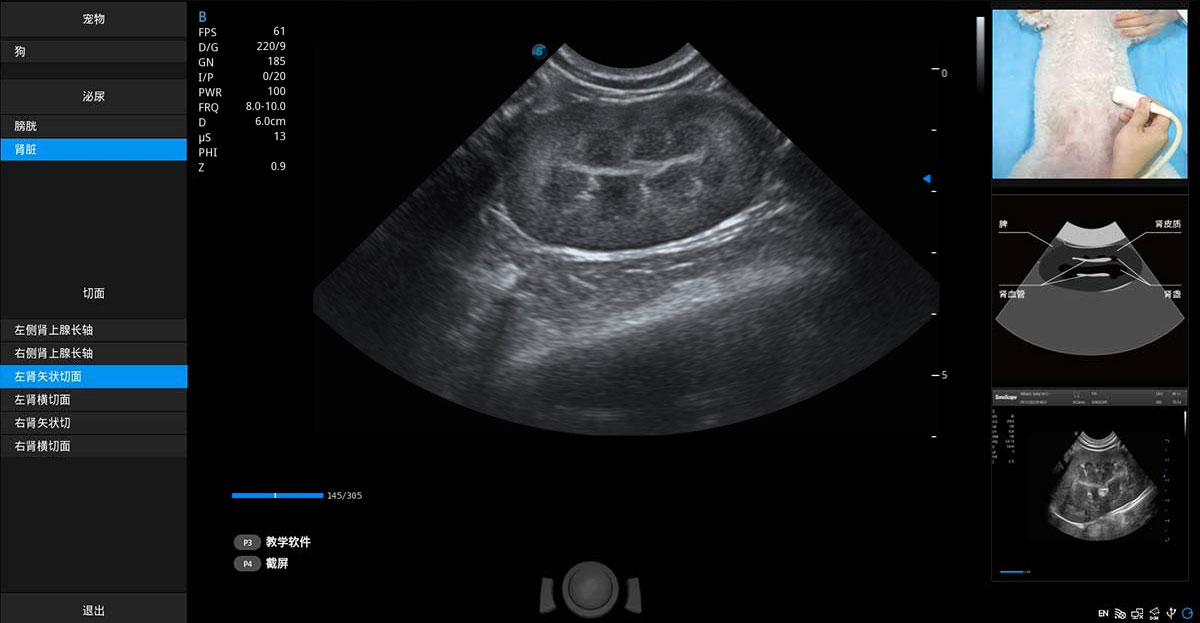

ProPet 70專為動(dòng)物醫(yī)生設(shè)計(jì),對(duì)不同的動(dòng)物體型和生理結(jié)構(gòu)作出了針對(duì)性的優(yōu)化。通過(guò)動(dòng)物影像專用軟件,可滿足個(gè)性化的應(yīng)用需求,幫助動(dòng)物醫(yī)生獲得更精確的診斷數(shù)據(jù)。

為精細(xì)結(jié)構(gòu)及組織邊緣提供高清晰度的圖像和更大的成像視野。幫助減輕醫(yī)生的用眼疲勞,快速精準(zhǔn)獲得測(cè)量的數(shù)據(jù)。

提供解剖示意圖、標(biāo)準(zhǔn)超聲圖像、掃查手法圖和操作者實(shí)時(shí)檢查圖像,指導(dǎo)操作者進(jìn)行標(biāo)準(zhǔn)切面的正確掃查。